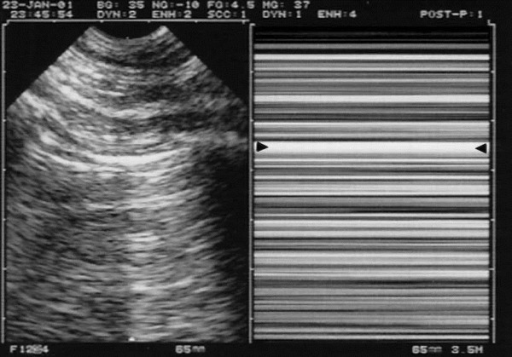

Lung views

The opposition of pleural and aerated lung below it produces a characteristic image as the parietal and visceral pleura slide against each other, often described as “marching ants”. An M-mode spike through the intercostal window will produce another characteristic temporal image known as the “seashore sign”.

In the setting of pneumothorax, the M-mode image will become a “barcode sign”. This view is less valuable in the identification of haemothorax or other intrapleural free fluid, they are probably better looked for at the diaphragm in the RUQ and LUQ views.

Right: M-mode, the abolition of lung sliding is visible as the “Barcode sign”. The arrows indicate the pleural signal. Lichtenstein DA - CC-BY 3.0 Link